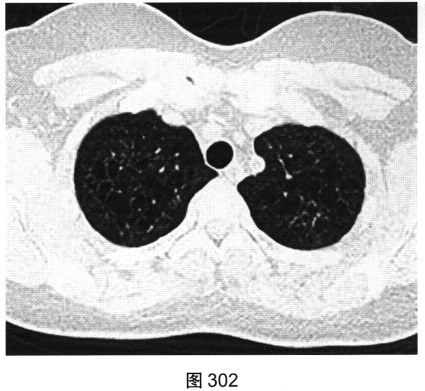

- [材料题] 患者女性,32岁,因“间断刺激性干咳1年,发现肺部囊性病变8个月”就诊。患者无发热、咯血、胸痛、呼吸困难。服甘草片、阿莫西林无明显好转。胸部HRCT如图302~图307所示。

- 多项选择题1.患者胸部HRCT的阳性征象有( )

- 多项选择题2.影像检查所示肺内主要病变的形态、分布特点为( )

A、囊状透亮影形状不规则、大小不一

C、囊状透亮影形状规则,大小及肺内分布均匀

G、囊壁较薄、略欠均匀,部分囊壁欠连续